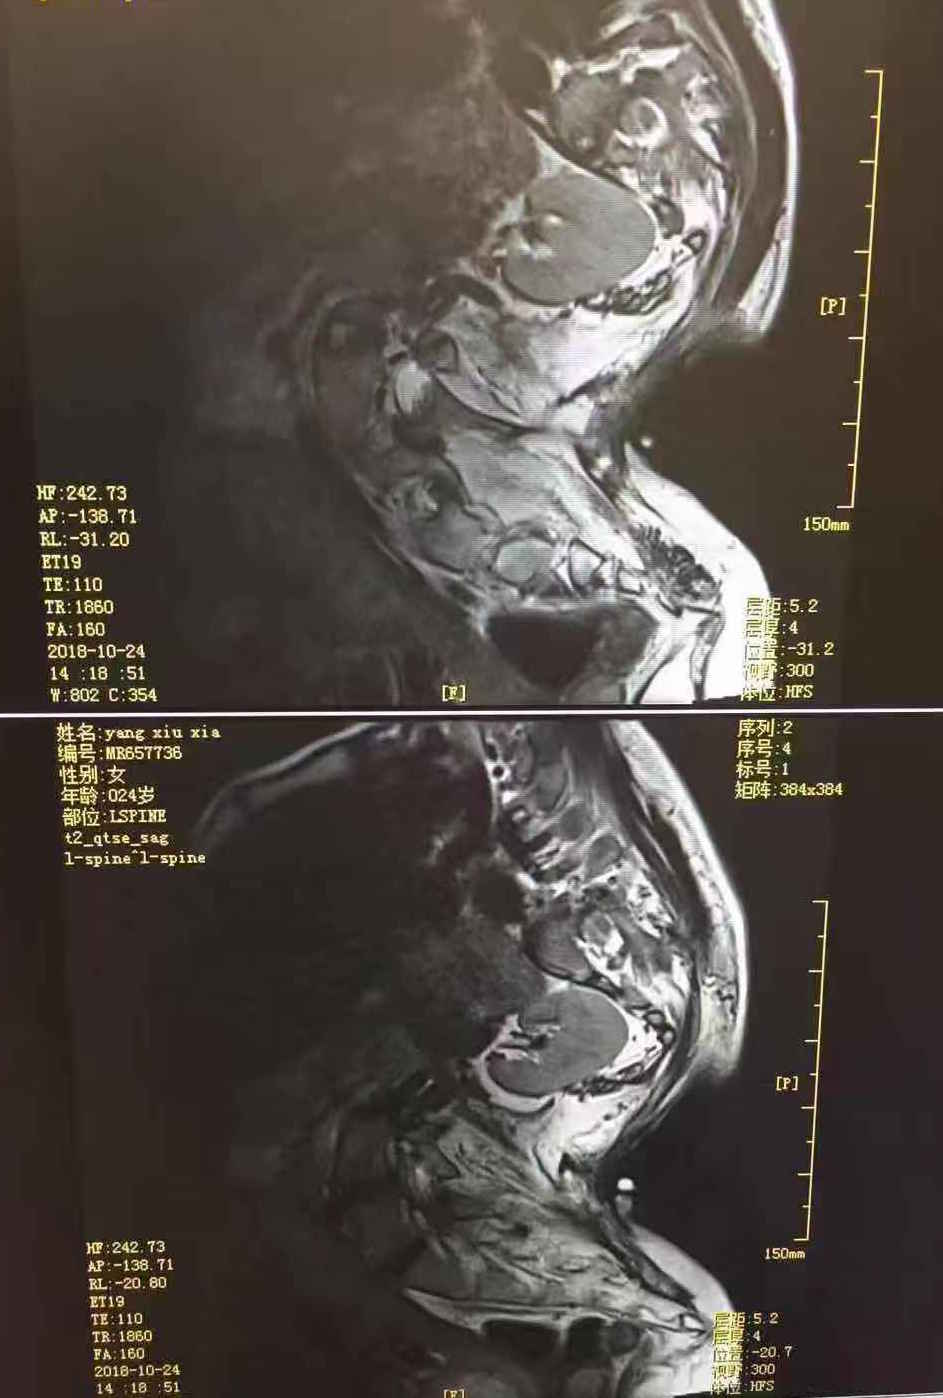

近日,我院收治了一位严重胸廓腰椎畸形的36+6周孕妇。该患者身高只有130cm,腰部瘢痕挛缩、胸廓脊柱严重畸形、重度肺功能障碍,脊柱解剖改变。腹中胎儿虽然带给她生命的希望,但同时加重其呼吸困难。术前麻醉科黄瀚副主任带领医疗团队对该孕妇进行了详细的评估并进行全科讨论,完善腰椎MRI检查,并与产科胡雅毅教授团队反复讨论,拟定对于这例患者以及腹中胎儿最适合的麻醉方式。